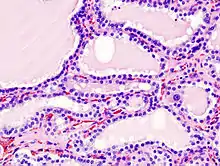

Hyperthyroidism is one of the most common endocrine conditions affecting older domesticated housecats. In the United States, up to 10% of cats over ten years old have hyperthyroidism.[61] The disease has become significantly more common since the first reports of feline hyperthyroidism in the 1970s. The most common cause of hyperthyroidism in cats is the presence of benign tumors called adenomas. 98% of cases are caused by the presence of an adenoma,[62] but the reason these cats develop such tumors continues to be studied.

The most common presenting symptoms are: rapid weight loss, tachycardia (rapid heart rate), vomiting, diarrhea, increased consumption of fluids (polydipsia), increased appetite (polyphagia), and increased urine production (polyuria). Other symptoms include hyperactivity, possible aggression, an unkempt appearance, and large, thick claws. Heart murmurs and a gallop rhythm can develop due to secondary hypertrophic cardiomyopathy. About 70% of affected cats also have enlarged thyroid glands (goiter). 10% of cats exhibit "apathetic hyperthyroidism", which is characterized by anorexia and lethargy.[63]